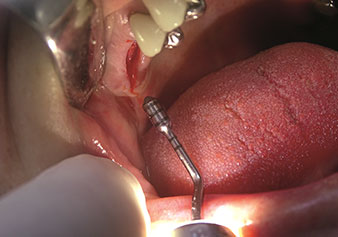

One application, which is often underestimated is the atraumatic extraction of tooth roots or root fragments in the scope of alveolar management. The fine periotomes, which are currently available in two versions (EX1 and EX2 from W&H), can also be used to remove teeth which have previously undergone special endodontic treatment or ankylosed roots with ease. This results in extraction alveoli where both the hard and soft tissue are fully intact as it is generally possible to avoid reflection.

This establishes the optimal basis for subsequent or immediate implant treatment (Figures 1 and 2 included with the kind permission of Dr Torsten Conrad, Bingen a. Rhein).

Situation following piezosurgical extraction

Fig. 2: Situation following piezosurgical extraction.

Photo: © Dr Torsten Conrad (Bingen am Rhein)